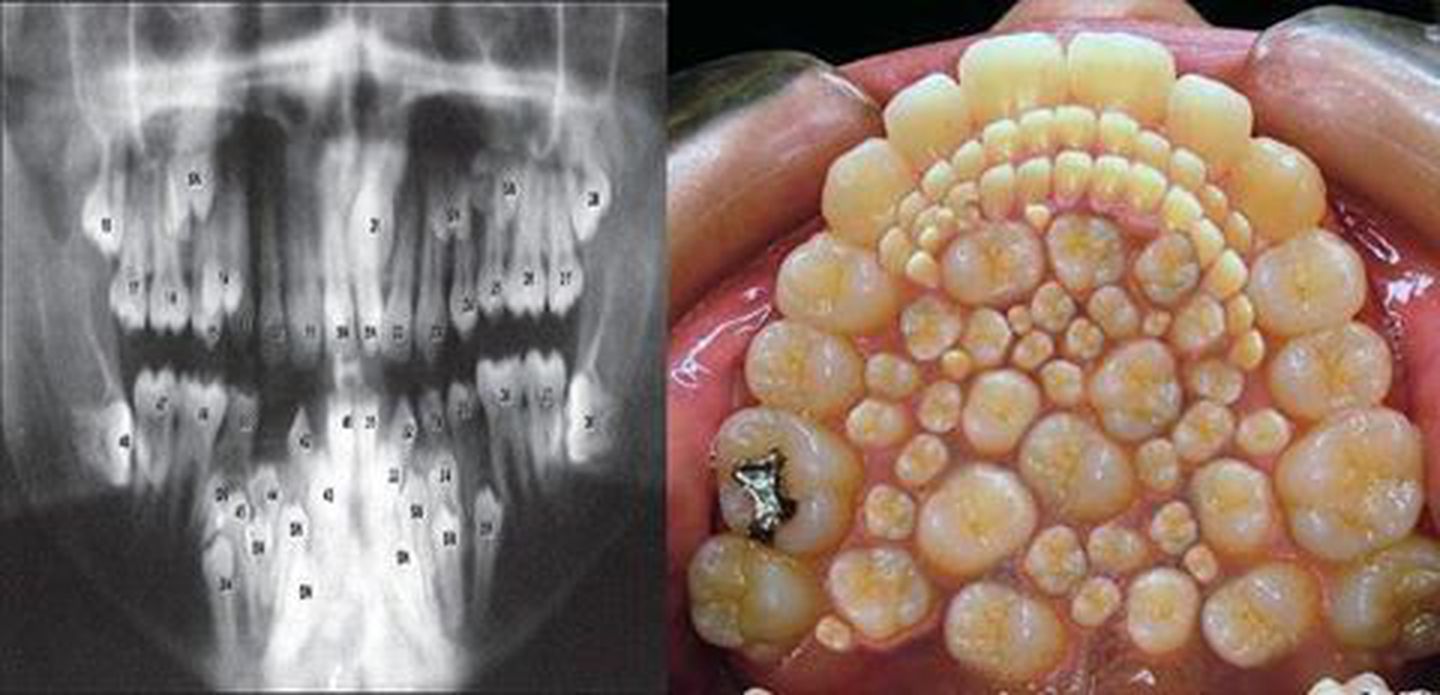

Hyperdontia is the condition of having supernumerary teeth or teeth that appear in addition to the regular number of teeth. They can appear in any area of the dental arch and can affect any dental organ. Usually affect the permanent teeth than the milk teeth. Their arrangement may be symmetrical or non-symmetrical. Causes could be hereditary in conditions of a single excess tooth or maybe associated with syndromes like the Gardners syndrome, Sturge-Weber syndrome or the Marfan's in case of many supranumarary teeth eruptions which is rare. It can also be associated with conditions like the cleft lip/palate and craniofacial dysplasia.